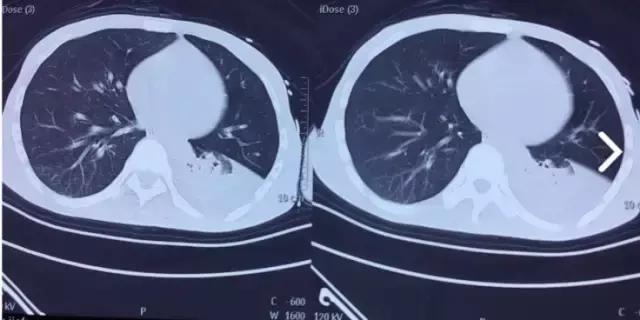

菅老师您好,非常抱歉,我们医院的核磁共振坏了几天了,复查的头部CT 未见明显异常,胸部CT 可见左侧胸腔积液明显,具体见下图,脑电图没有做,之后等修好了磁共振再给您结果,我想问,我们医院没有维生素B1注射剂,家属出去外购,这个药物只能肌肉注射,我要问的是,如果给予稀释后静脉滴注怎么样呢,通过肌注几支后,我感觉,症状有所好转,精神状态明显好转,只是抽搐还继续存在。

(部分CT图片)

情况已经了解具体意见如下供参考:.1肌肉注射的药物不能静脉注射。肺部改变,和我们当初分析的完全一致。颅脑核磁共振,还应该想办法做。做完了,以后我们应该能有所发现。保持联系,供参考。